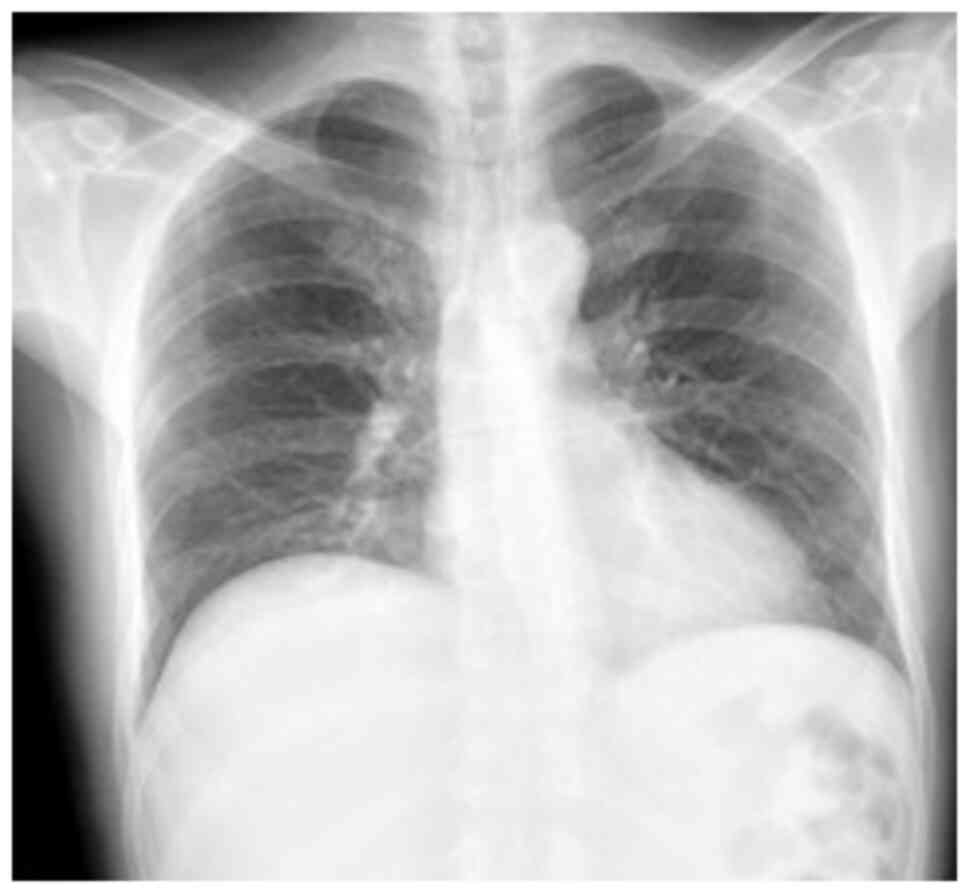

Complementary laboratory analyses were performed, yielding the following results: Leukocytes, 8,700/ml (normal range, 4,500-11,500/ml); neutrophils, 69% (normal range, 40-60%); hemoglobin, 10.6 g/dl (normal range, 13.8-17.2 g/dl); hematocrit, 32% (normal range, 40.7-50.3%); platelets, 353,000/ml (normal range, 150,000-400,00/ml); international normalized ratio (INR), 1.4 (normal value, 1); partial prothrombin time (PTT), 30.6 sec (normal range, 24.2-36.3 sec); prothrombin time (PT), 16.3 sec (normal range, 12.7-16.3 sec); creatinine, 0.86 mg/dl (normal range, 0.7-1.3 mg/dl); C-reactive protein, 20.8 mg/dl (normal, <10 mg/dl); CD4, 345 cells per mm3 (normal range, 200-500 cells per mm3); and an undetectable HIV viral load. A chest X-ray was performed, which revealed the elevation of the right hemidiaphragm, without pneumoperitoneum, without the presence of consolidations that suggested pneumonia or the presence of pleural effusion (Fig. 6).

Figure 6

Chest X-ray. A rise of the right hemidiaphragm is observed. Visible lung parenchyma without alterations. There is no pleural effusion.